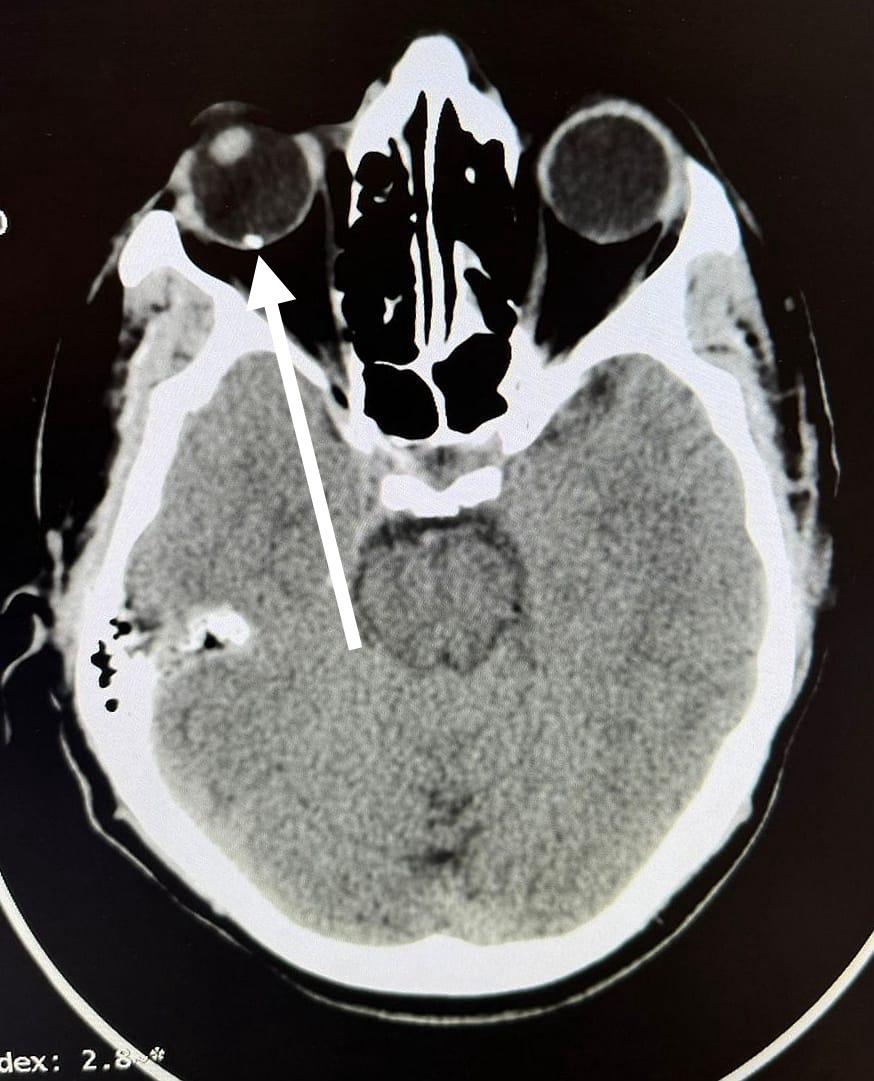

ومن جانبه أوضح الدكتور مجدي القاضي عميد كلية الطب البشري، أن قسم الطوارئ بالمستشفي الجامعي استقبل "عامل" يعمل في تقطيع الحديد بالصاروخ بدون استخدام اي وسائل حماية مما أدي الي دخول "شظية" اخترقت جميع طبقات العين وتسببت في تهتك في القرنية والعدسة والجسم الزجاجي لتستقر في الشبكية، مشيرًا الي ان المستشفي الجامعي تعد القبلة الاولي التي يقصدها جميع حالات الطوارئ من كافة الجهات وعلي مدار ٢٤ ساعة بالمجان علي نفقة الدولة او الخاضعين لمظلة التأمين الصحي.

ومن جانبه قال الدكتور محمود فاروق استاذ الشبكية، أن الفريق المعالج نجح إجراء عملية دقيقة اسفرت عن استئصال الجسم الزجاجي، والوصول الي قاع العين لإزالة الجسم الغريب وعمل كي للشبكية "بالليزر" لتجنب حدوث انفصال شبكي وتم انقاذ عين المريض من العمى المحقق.